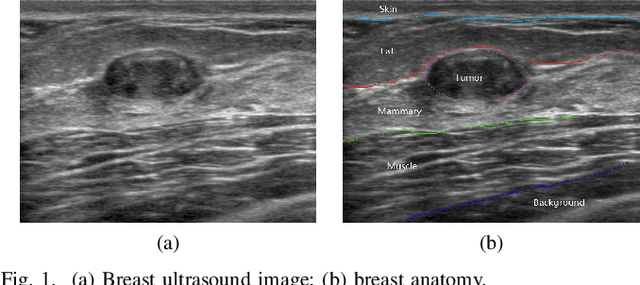

Abstract:Breast cancer is one of the most serious disease affecting women's health. Due to low cost, portable, no radiation, and high efficiency, breast ultrasound (BUS) imaging is the most popular approach for diagnosing early breast cancer. However, ultrasound images are low resolution and poor quality. Thus, developing accurate detection system is a challenging task. In this paper, we propose a fully automatic segmentation algorithm consisting of two parts: fuzzy fully convolutional network and accurately fine-tuning post-processing based on breast anatomy constraints. In the first part, the image is preprocessed by contrast enhancement, and wavelet features are employed for image augmentation. A fuzzy membership function transforms the augmented BUS images into fuzzy domain. The features from convolutional layers are processed using fuzzy logic as well. The conditional random fields (CRFs) post-process the segmentation result. The location relation among the breast anatomy layers is utilized to improve the performance. The proposed method is applied to the dataset with 325 BUS images, and achieves state-of-art performance compared with that of existing methods with true positive rate 90.33%, false positive rate 9.00%, and intersection over union (IoU) 81.29% on tumor category, and overall intersection over union (mIoU) 80.47% over five categories: fat layer, mammary layer, muscle layer, background, and tumor.

Abstract:Breast cancer is one of the leading causes of cancer death among women worldwide. In clinical routine, automatic breast ultrasound (BUS) image segmentation is very challenging and essential for cancer diagnosis and treatment planning. Many BUS segmentation approaches have been studied in the last two decades, and have been proved to be effective on private datasets. Currently, the advancement of BUS image segmentation seems to meet its bottleneck. The improvement of the performance is increasingly challenging, and only few new approaches were published in the last several years. It is the time to look at the field by reviewing previous approaches comprehensively and to investigate the future directions. In this paper, we study the basic ideas, theories, pros and cons of the approaches, group them into categories, and extensively review each category in depth by discussing the principles, application issues, and advantages/disadvantages.

Abstract:Breast ultrasound (BUS) image segmentation is challenging and critical for BUS Computer-Aided Diagnosis (CAD) systems. Many BUS segmentation approaches have been proposed in the last two decades, but the performances of most approaches have been assessed using relatively small private datasets with differ-ent quantitative metrics, which result in discrepancy in performance comparison. Therefore, there is a pressing need for building a benchmark to compare existing methods using a public dataset objectively, and to determine the performance of the best breast tumor segmentation algorithm available today and to investigate what segmentation strategies are valuable in clinical practice and theoretical study. In this work, we will publish a B-mode BUS image segmentation benchmark (BUSIS) with 562 images and compare the performance of five state-of-the-art BUS segmentation methods quantitatively.